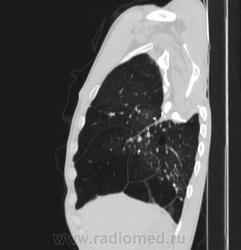

Состояние после торакопластики.

Молодой человек 30 лет, в 04 году выявлен фиброзно-кавернозный ТБ, в течение 12 месяцев лечился в стационаре, прооперирован-5реберная торакопластика справа, через 3 года переведен в 3ГДУ, в 10году снят с ДУ по излечению. Пришел провериться по ухудшению состояния. На КТ легких данных за рецидив ТБ, вроде нет. С " торакопластикой" был единственным пациентом на учете.

Состояние после правосторонней 5-реберной торакопластики по поводу ФКТ.Грубые остаточные изменения:поликистоз,буллезно-дистрофические изменения,плевропневмоцирроз правого легкого..Нет ли  мелкоочаговой диссеминации в обоих легких?Нужен Rархив.(ПТД).